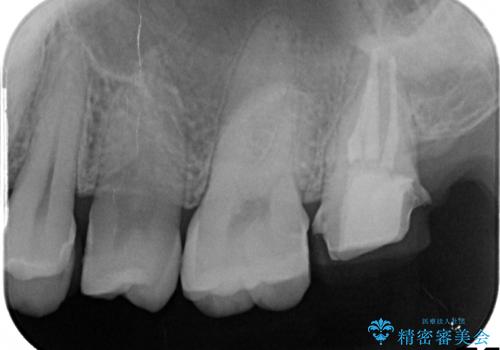

→土台を築造後、かぶせ物を製作する

奥歯が感染をおこし強い痛みを出してしまっていたため、顕微鏡を用いた根管治療をおこない根管内を洗浄した後かぶせ物を製作しました。

ひとつひとつの治療を丁寧に行うことで今後も長く使う事ができます。